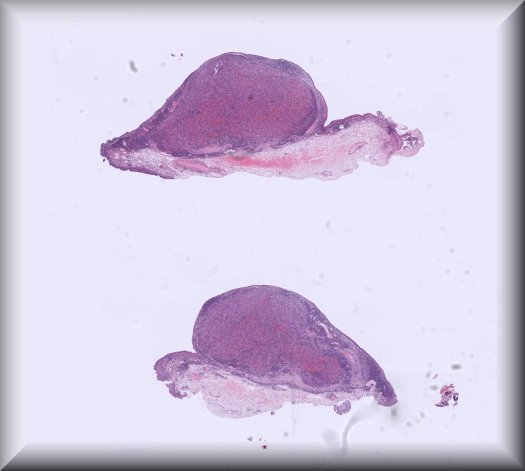

Yamini Krishna (Liverpool): A 78-year old Greek lady presenting with two painless, red bulbar conjunctival masses in the left eye. Previous complicated cataract surgery in that eye. No change vision. Right eye normal. Systemically otherwise well. |

||